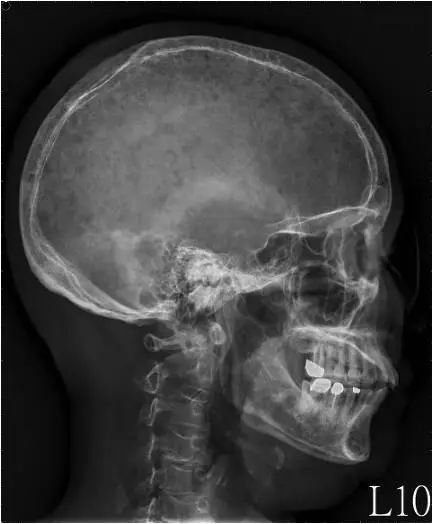

本題提供兩張頭顱 X 光片(正面 AP view 與側面 Lateral view):

側面觀(Lateral view): 側面更清晰呈現整個顱蓋骨(calvarium)廣泛分布的多發性圓形溶骨性病灶,大小從數毫米到超過 1 公分不等,散布如「雨滴打在頭顱上」的外觀——即典型的「雨滴頭顱(raindrop skull / pepper-pot skull)」。病灶無鈣化、無硬化邊、無骨膜反應,與轉移性骨腫瘤的混合型病灶